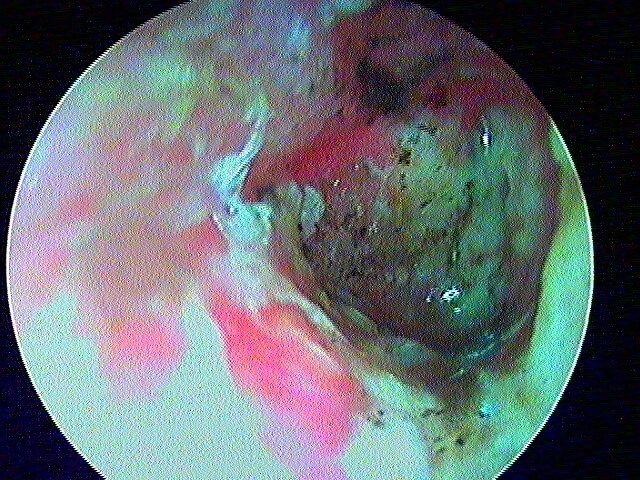

10/1 Cholestéatome acquis (secondaire)

Epithélium stratifié, kératinisé et squameux présent dans l’oreille moyenne, "croissance progressive de peau dans l’oreille", "skin in the wrong place": la peau malade du tympan va détruire tout sur son passage: le tympan lui-même, les osselets, le cadre osseux jusqu'à la méninge. Là il faut bien utiliser toutes ses connaissances sémiologiques d'otoscopie pour faire le diagnostic, qui est plus facile que l'otite atéléctasique, en raison de la présence de squames.

Cela touche adultes & enfants.

Le/la patient·e avait attendu quelques mois avant de revenir: le cholestéatome a englobé tout le malléus: